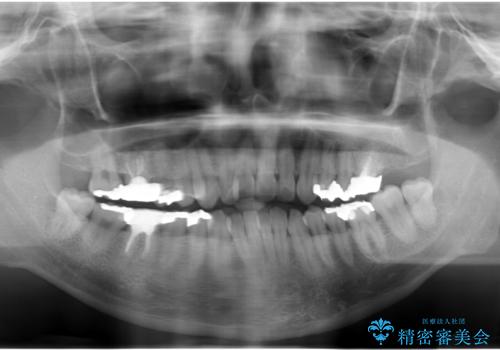

- 突き出た前歯の角度の改善と虫歯治療の改善を求めて来院されました。

虫歯を除去したのち、マウスピース矯正治療を行い、歯並びやがたつきを改善したのち、セラミックに置き換えることで審美性の向上を計画します。